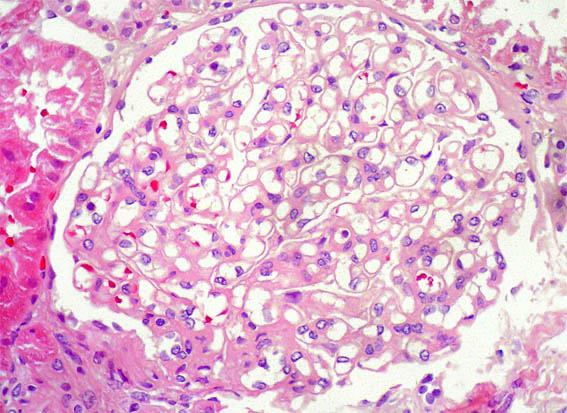

H&E, X400.

Figura 5.